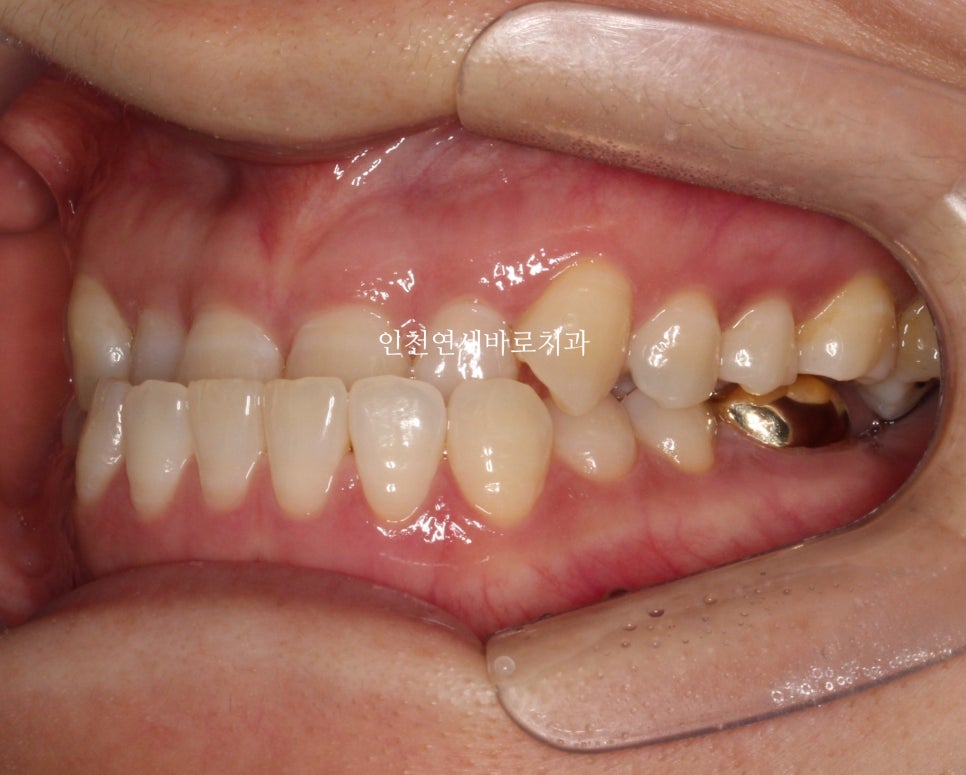

초진 시 상태

처음 오셨을 때 사진